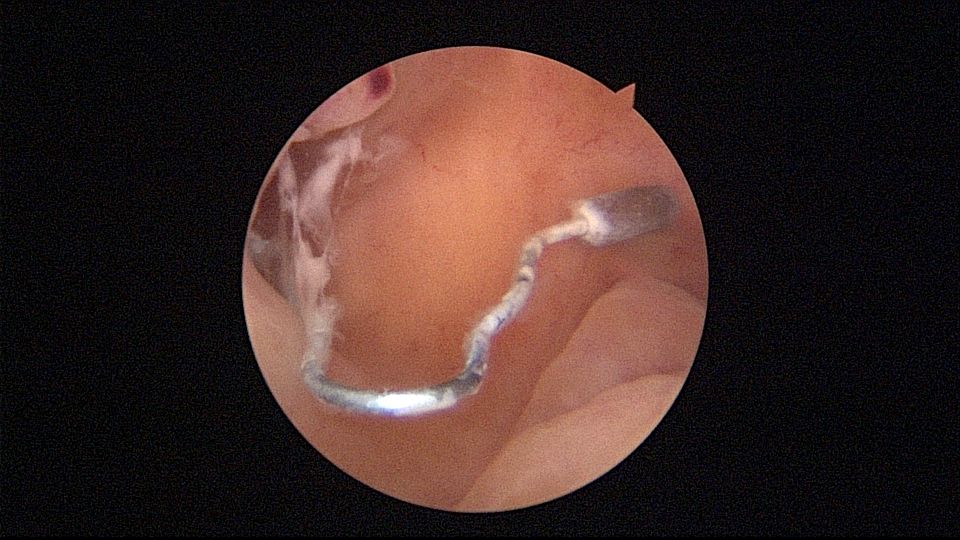

很有意思的一次取环经历:患者33岁,G2P1,剖宫产1次。安环7年,月经淋漓不尽3个月,2家医院取环失败,两次取环时间相隔24天,第二次取环失败后第二天到我院行宫腔镜取环。子宫后倾后屈位,剖宫产切口憩室处组织杂乱,爱母环位置正常,感觉是个比较简单的取环,取环钩探寻节育环,顺利取出。用刮匙准备诊刮,刮匙很容易进入,感觉很深,达13cm,但前面宫腔镜检查没有异常,以为是B超测量子宫有误,或者剖宫产粘连把子宫拉上去了,没有往子宫穿孔方面想,刮匙试探几次均是相同结果,试着刮了几下,没有内膜组织,再次置镜检查,结果镜子进入盆腔,看见网膜脂肪组织。宫颈内口闭塞,花了较多时间也进不去宫腔,穿孔处无出血,盆腔无积血,放弃诊刮。打电话给第二家取环医院的医生,得知前一天取环时感觉穿孔,放弃取环,介绍到我这里宫腔镜取环。分析整个过程,第一家医院在切口憩室处已穿孔,取环失败,穿孔处虽然愈合,却是一个薄弱环节,第二家医院和我们的宫腔镜均在该处进入盆腔,刮匙探查有底,是因为刮匙抵到了骶骨。